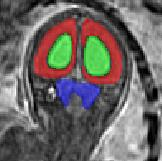

Limiting failures of machine learning systems is of paramount importance for safety-critical applications. In order to improve the robustness of machine learning systems, Distributionally Robust Optimization (DRO) has been proposed as a generalization of Empirical Risk Minimization (ERM). However, its use in deep learning has been severely restricted due to the relative inefficiency of the optimizers available for DRO in comparison to the wide-spread variants of Stochastic Gradient Descent (SGD) optimizers for ERM. We propose SGD with hardness weighted sampling, a principled and efficient optimization method for DRO in machine learning that is particularly suited in the context of deep learning. Similar to a hard example mining strategy in practice, the proposed algorithm is straightforward to implement and computationally as efficient as SGD-based optimizers used for deep learning, requiring minimal overhead computation. In contrast to typical ad hoc hard mining approaches, we prove the convergence of our DRO algorithm for over-parameterized deep learning networks with ReLU activation and a finite number of layers and parameters. Our experiments on fetal brain 3D MRI segmentation and brain tumor segmentation in MRI demonstrate the feasibility and the usefulness of our approach. Using our hardness weighted sampling for training a state-of-the-art deep learning pipeline leads to improved robustness to anatomical variabilities in automatic fetal brain 3D MRI segmentation using deep learning and to improved robustness to the image protocol variations in brain tumor segmentation. Our code is available at https://github.com/LucasFidon/HardnessWeightedSampler.